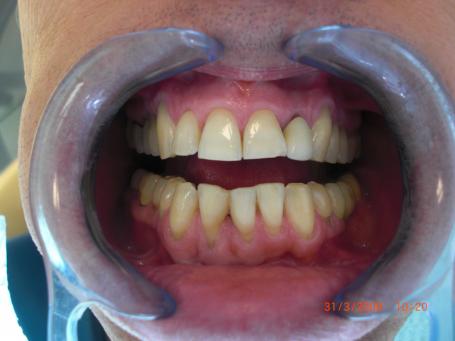

2°)Préparation du moignon dentaire.

La couronne iatrogène est déposée et le moignon est retaillé de sorte à placer les limites de la prochaine couronne dentaire sous gingivale.Une empreinte dentaire en 2 temps est réalisée.La dévitalisation dentaire étant satisfaisante, on décide de conserver le traitement de canal d'origine car il y a plus de risque de fracture sur cette dent très frêle.